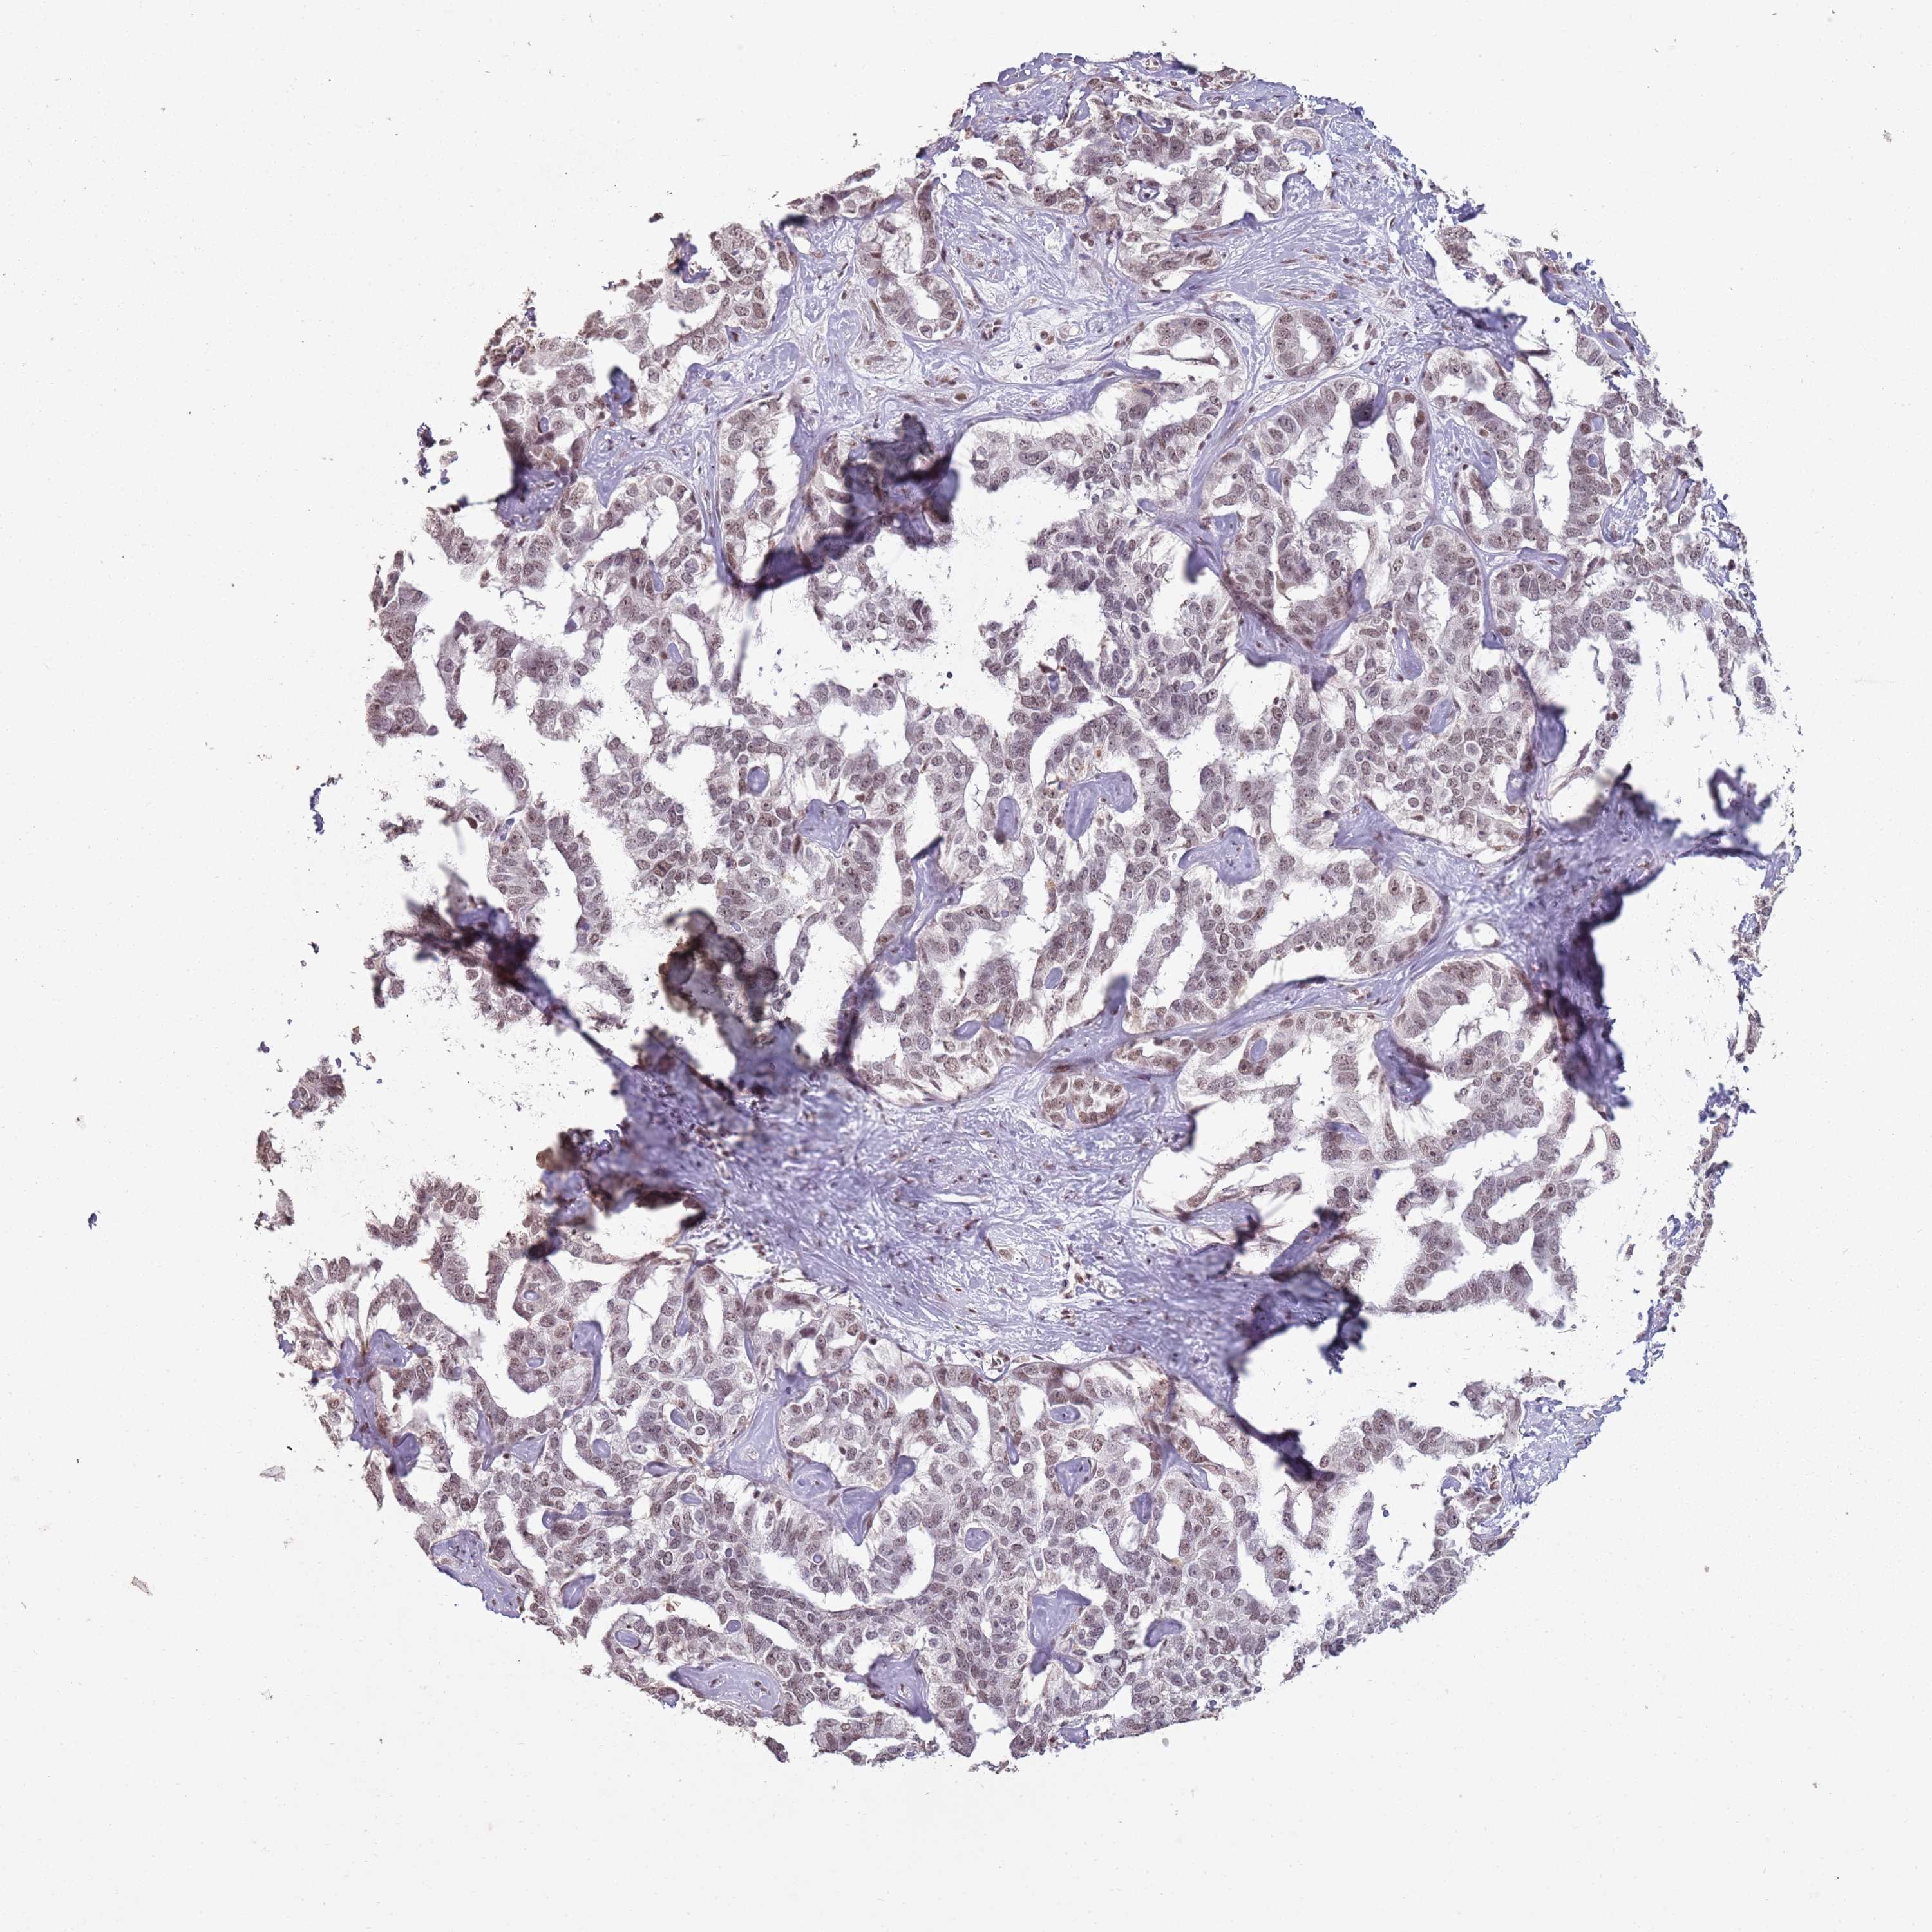

LIVER CANCER - Protein expressioni

A mouse-over function shows sample information and annotation data. Click on an image to view it in a full screen mode. Samples can be filtered based on level of antibody staining by selecting one or several of the following categories: high, medium, low and not detected. The assay and annotation is described here.

Note that samples used for immunohistochemistry by the Human Protein Atlas do not correspond to samples in the TCGA dataset.

Antibody stainingi

Antibody staining in the annotated cell types in the current human tissue is reported as not detected, low, medium, or high, based on conventional immunohistochemistry profiling in selected tissues. This score is based on the combination of the staining intensity and fraction of stained cells.

Each image is clickable and will lead to virtual microscopy that enables deeper exploration of all samples and also displays staining intensity scores, fraction scores and subcellular localization as well as patient and tissue information for each sample.

Antibody HPA039634

Antibody HPA048127

Cholangiocarcinoma

Carcinoma, Hepatocellular, NOS